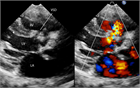

1. 乳幼児で心雑音を聴取した場合、先天性心疾患を念頭に置く必要があり、心臓超音波検査を行う。心臓超音波検査ができない場合は専門医に紹介する(推奨度1)

1. 心室中隔欠損は、欠損孔の部位により、膜性周囲部(perimembranous)、筋性部(muscular)、漏斗部または肺動脈弁下部(subarterial)に分類され、自然歴、手術適応が各々異なるため、部位診断は重要である。

1. 心室中隔欠損は自然閉鎖する場合もあるが、心不全症状を有する、あるいは肺高血圧を合併する場合、漏斗部欠損で大動脈弁の逆流を呈する場合は、外科手術の適応となる(推奨度1)。Eisenmenger症候群を呈すると手術適応がなくなるので、その前に適切な治療時期を逃さないことが大切である。